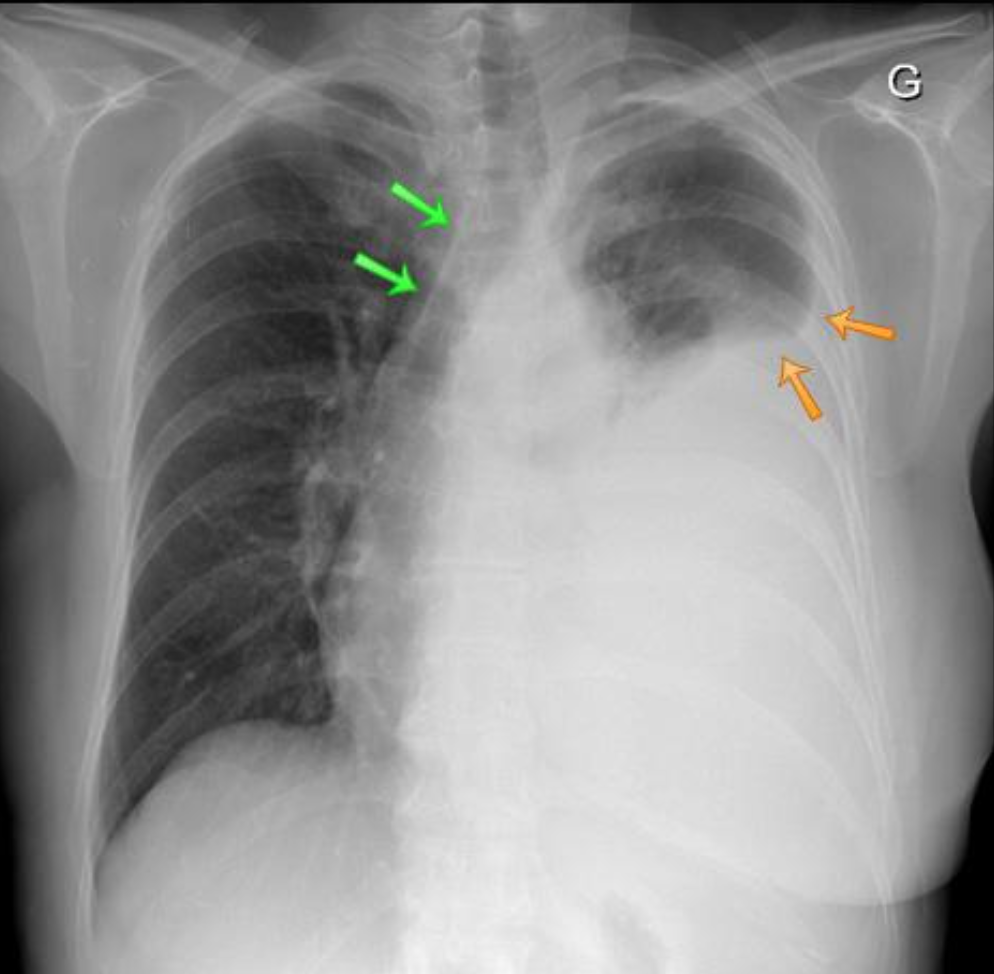

Un cycliste de 25 ans est admis en salle de réanimation à la suite d’une collision avec une voiture.

L’ABC révèle un patient en choc. Il y a une diminution du murmure vésiculaire à l’hémithorax gauche.

Sur cette radiographie pulmonaire, quelle est l’anomalie principale ? Soyez précis.

A

Épanchement pleural gauche, vraisemblablement un hémothorax. Fractures de côtes gauches associées.

Remarquer les signes suivants:

• hypotransparence (« trop blanc ») de l’hémithorax gauche

• signe de la silhouette avec la coupole diaphragmatique gauche et le rebord cardiaque gauche

• atélectasie passive presque complète du poumon gauche

• déplacement cardio-médiastinal controlatéral (flèches vertes sur la trachée déviée)

• fractures de côtes gauches (flèches orangées)